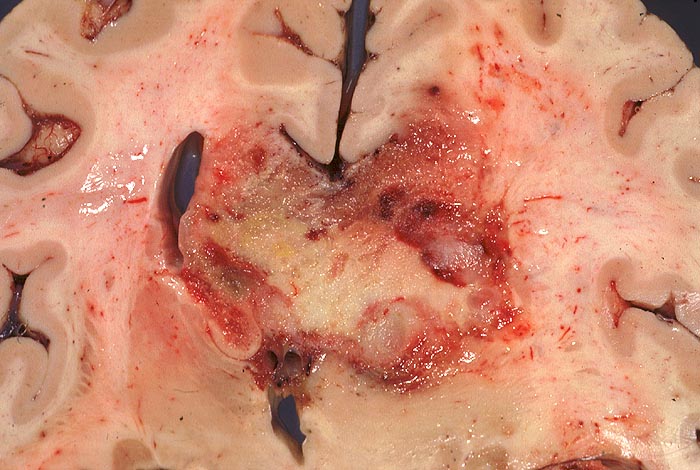

PathoPic – image database / PathoPic ID 946 - Glioblastoma multiforme

Glioblastoma multiforme

Hirn parietal

Bunter unscharf begrenzter schmetterlingsförmiger Tumor. Der Tumor überschreitet die Mittellinie im Bereich des Balkens und infiltriert beide Hemisphären. Intraventrikuläre Tumorausbreitung rechts.

Makroskopie